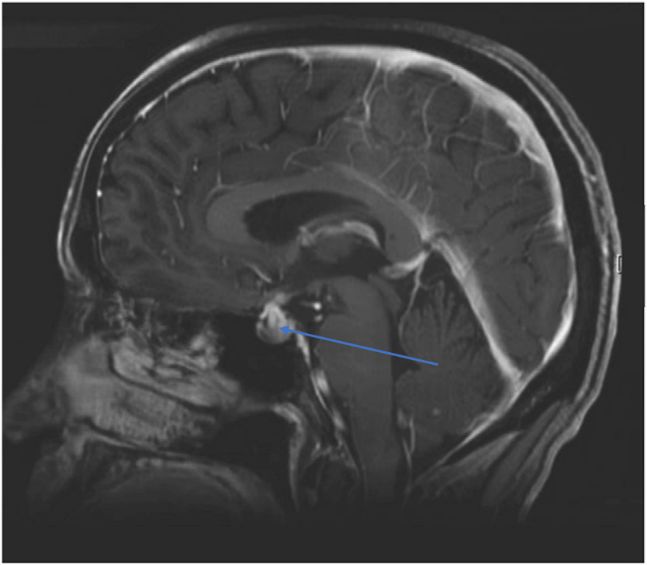

最常见于CTLA-4抗体(ipilimumab)治疗的患者,3mg/kg剂量组发生率≤10%,10mg/kg剂量组发生率17%;ipilimumab联合nivolumab发生率≤13%[1,2,3,4,5]。从开始使用ipilimumab到发生垂体功能减退的中位时间为8-9周[6,7]。症状包括头痛(约85%)和乏力(约66%)。如果甲状腺功能检查提示TSH和FT4均降低,则需高度怀疑垂体功能减退,最常见的是中枢性甲状腺功能减退(>90%),其次是中枢性肾上腺功能不全[8,9,10]。约75%患者会同时出现中枢性甲状腺功能减低和中枢性肾上腺功能减退;50%的患者会出现全垂体功能减退(包括肾上腺功能减退合并甲状腺功能减退和性腺功能减退)[10-12]。影像学检查垂体MRI可见垂体增大,垂体柄增厚、鞍区上凸、腺体信号不均匀强化等。

如果怀疑垂体功能减退的患者,需要进一步检测明确诊断。推荐的检查包括早晨8点甲状腺功能(TSH和FT4)、肾上腺功能(8am、4pm和12am的昼夜ACTH、皮质醇节律)、性腺功能(睾酮、雌激素、卵泡刺激素FSH、黄体生成素LH)、垂体鞍区MR。必要时请内分泌专科会诊。